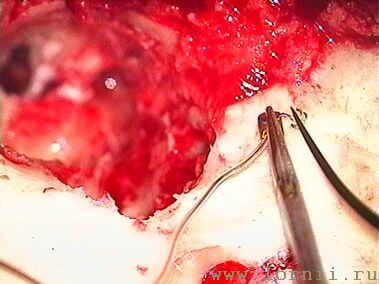

У пациентов с аномалией развития уха и после радикальной операции катушка импланта была установлена в круглое окно (рис. 13, 15, 16). Для этого крепление катушки подворачивали (рис. 14). Далее укладывали фасцию височной мышцы в нишу окна улитки (рис. 15), затем на фасцию устанавливали катушку импланта и подворачивали края фасции. Фиксация конструкции обеспечивалась полоской аутохряща из ушной раковины пациентки (рис. 16).